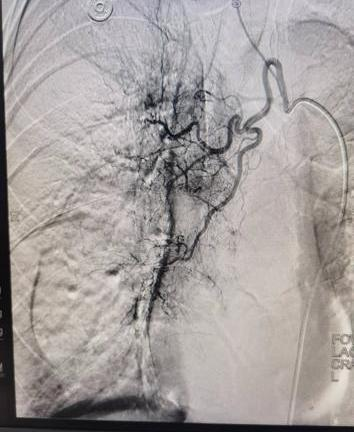

案例二:魏先生,64岁,肾恶性肿瘤术后肝、肺转移。2025年11月3日,在DSA引导及局麻下行经导管支气管动脉联合肝动脉造影、栓塞+灌注化疗术,实现多部位协同治疗。

支气管动脉造影                                                                    肝动脉造影